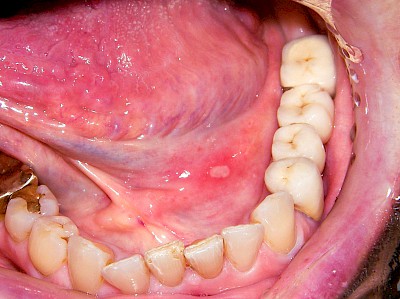

Herpes-Bläschen können ebenfalls kleine Gruppierungen von Bläschen zeigen, die dann aber – zumindest zu Beginn – streng auf einer Seite lokalisiert sind. Herpes-Viren ziehen sich nach Erstinfektion in bestimmte Strukturen der Nerven-Gewebe (Spinalganglien) zurück und können unter besonderen Bedingungen (nach Stress-Situationen, nach Sonnenexposition...) wieder "ausbrechen". Herpes-simplex Viren zeigen sich bei vielen Menschen an den Lippen. Seltener sind Schleimhautbereiche im Mund (am ehesten noch der Gaumen) betroffen. Manchmal sind auch Herpes-Zoster-Viren die Ursache.

Beispiele13 Bilder